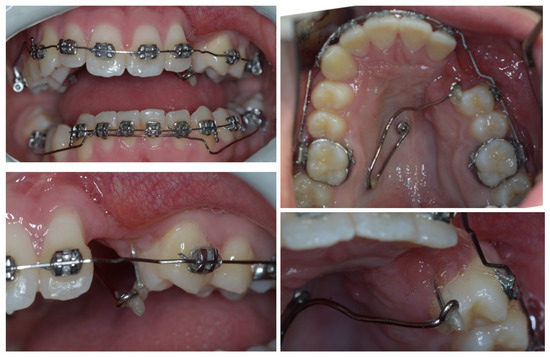

4. Follow-Up and Outcomes